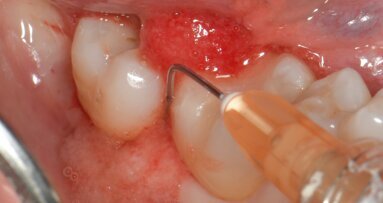

Dopo l’anestesia locale, è stato scollato un lembo a spessore totale e il dente estratto in modo atraumatico (Fig. 1). Successivamente, l’alveolo post-estrattivo è stato zeppato con granuli di osso bovino decellularizzato (Re-Bone®, Ubgen, Padova/Italy) e utilizzata una membrana di pericardio bovino come barriera (Shelter® Membrane, Ubgen, Padova/Italy) (Fig. 2).